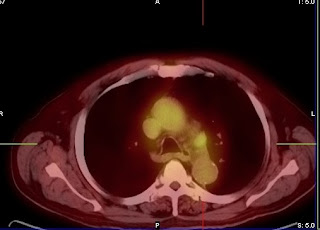

stage iiia?